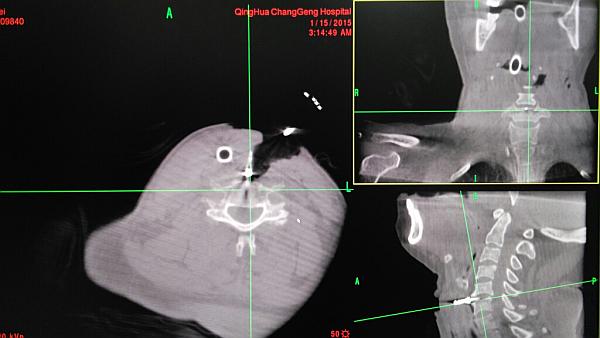

术前O-ARM定位颈5-6椎间盘节段

定位针再次确定颈5-6椎间盘位置并再次确定导航计划

术中O-ARM确定人工椎间盘位置好